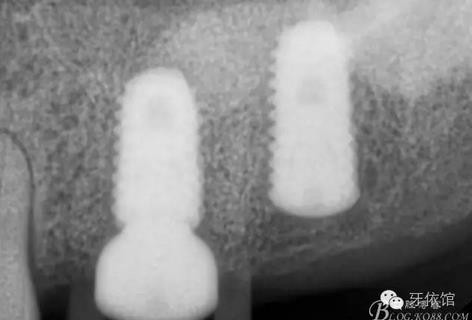

X光片

術(shù)后x光片,右上6直接上愈合基臺,但未完全就位,右下7手術(shù)過程略

這是術(shù)后1月的片子,重新就位愈合基臺